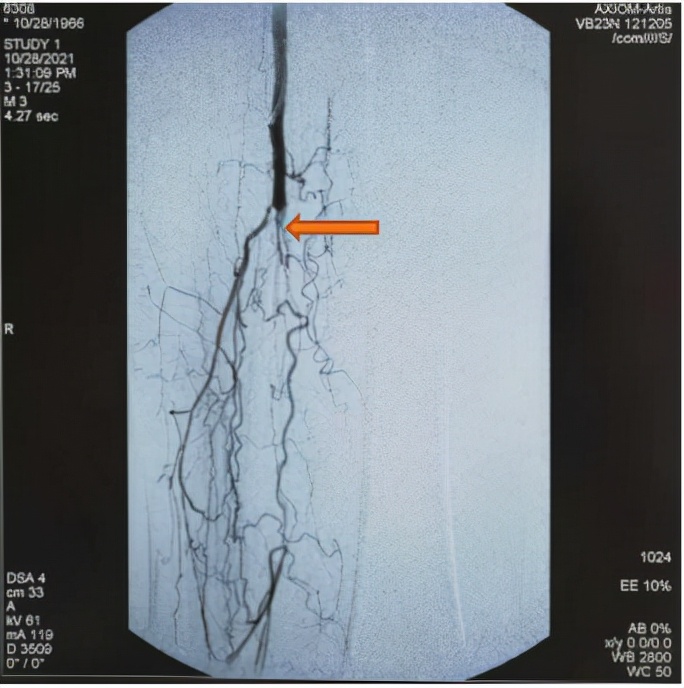

术中造影

术中给患者静脉抗凝药,经健侧股动脉穿刺造影了解血管闭塞情况并确定治疗方案,在透视下未见清晰的血管流出道,也不见腘动脉、胫前后动脉、腓动脉,只在现有的血管真腔和假腔进行了球囊扩张。考虑患者如果下肢血管不通畅以后将会面临截肢的风险,市十院介入科团队再次仔细研究患者透视下的图像,最终找到下肢动脉血管的阻塞远端并进行造影,发现有血流通过足背外侧,引入导丝进行了支架植入并进行了球囊扩张。术后老李患者生命体征平稳,疼痛感也逐渐消失。患者家属了解到术中的情况,对介入团队医生的坚守和不放弃表示感激。